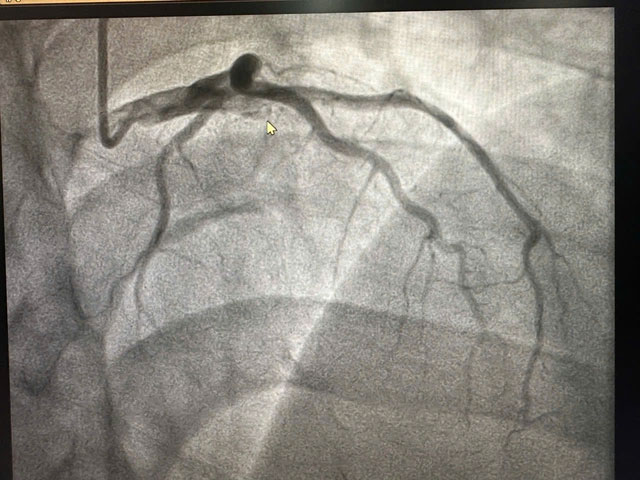

Khi chụp mạch vành, các bác sĩ phát hiện bệnh nhân bị tắc cụt hoàn toàn động mạch liên thất trước từ đoạn đầu, diện nhồi máu rất lớn, lý giải phần nào cho việc bệnh nhân đi vào sốc sớm.

Theo BS Việt Anh, may mắn, sau 45 phút can thiệp, mạch vành tắc đã được tái thông, bệnh nhân tạm thời qua cơn nguy kịch.